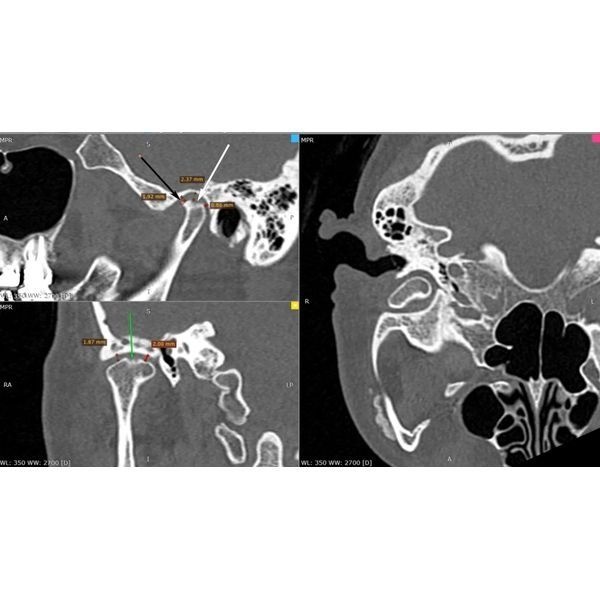

Конусно-лучевая компьютерная томография (КЛКТ) показала:

- очаги разрушения костной ткани в области корней зубов 2.7 и 1.7 — кисты, периодонтит;

- почти идеальное строение левого сустава — суставная головка округлая, с чёткими границами, но суставная щель заметно меньше нормы, т. е. челюсть смещена назад и вверх;

- изменения в правом суставе — деформация суставной головки в сочетании с узурами (эрозиями), участок перестройки костной ткани с «клювовидным» выступом, смещение головки назад;

- однородное заполнение большинства корневых каналов рентгеноконтрастным материалом.